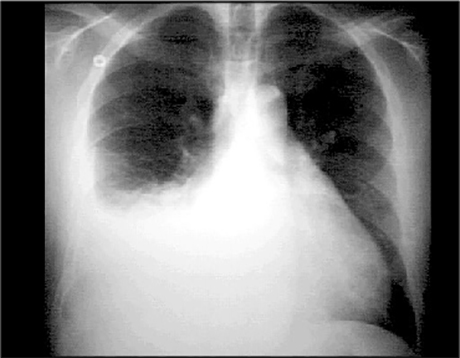

You are incorrect - the best interpretation of the chest X ray in our patient is pulmonary venous congestion.

This chest X ray shows a pleural effusion. In this PA view, it is demonstrated by a large opaque shadow with a concave upper border that obscures the diaphragm, heart border and half of the lung field on the right side. The left side shows no evidence of effusion. Note the straightening of the left heart border that suggests left atrial enlargement.